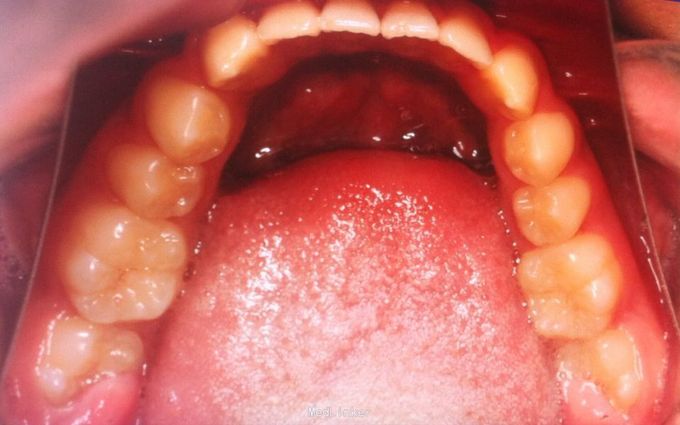

恒牙期 磨牙中性关系 前牙覆合覆盖关系正常 A1B1之间1mm间隙